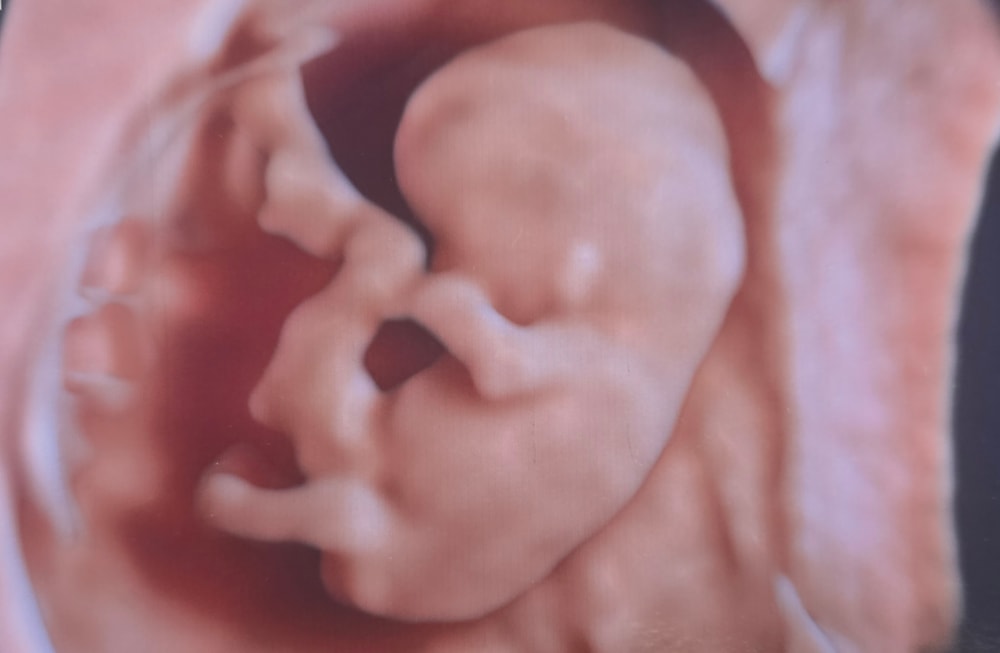

Сходили вместе на узи, посмотреть малыша, послушали сердцебиение. С малышом все хорошо.